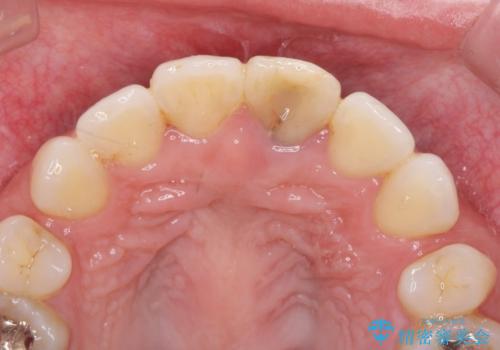

変色してきた前歯をセラミック治療

- 神経の治療をしたまま放置していた歯が、変色してきたので改善したい。と前歯の審美性の改善を求めて来院されました。

根管治療後の歯には部分的な修復処置が為され、変色が進行している状態でした。

ジルコニアクラウンを用いて、自然な色調となるよう治療を計画します。

根管治療は行わず、仮歯・ジルコニアクラウンのみの処置を行い自然な歯に仕上げることができました。